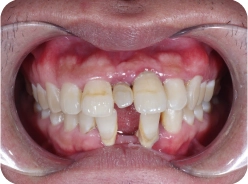

• Upper jaw porcelain crown is damaged and infected

Complications from poorly performed porcelain dentures and the use of low-quality porcelain materials caused Ms. Ly Phan to endure prolonged pain due to infection and unpleasant mouth odor.

To protect her real teeth and resolve her concerns, Dr. Tin decided to remove all of the old porcelain dentures, treat the infection, and wait until the teeth had recovered before placing new porcelain crowns.

Thanks to the doctor’s expertise, the entire process of removing the old dentures and restoring the new ones was smooth and painless for Ms. Ly Phan.

Initially, I only needed to restore my damaged upper teeth. However, because of Dr. Tin comfort performance, I decided to get my lower jaw restored with porcelain crowns too.